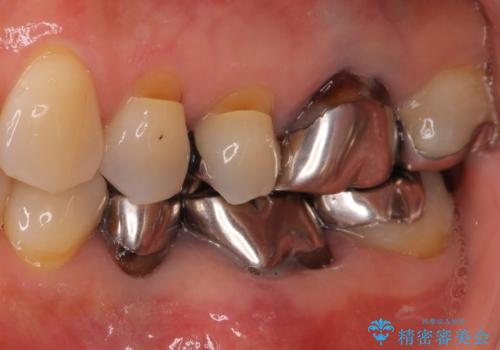

- 口腔内にある銀歯を全て外したいとのことで来院された患者様です。

土台に含まれている金属も含め、口腔内の金属は全て除去し、抜歯しなければならない歯は抜歯し、オールセラミッククラウンやセラミックインレーにて治療することとしました。

上下奥歯の抜歯を同時期に行わず、下顎の治療を終えてから上顎を抜歯して治療を進めたため、1年ほどの期間を要しました。